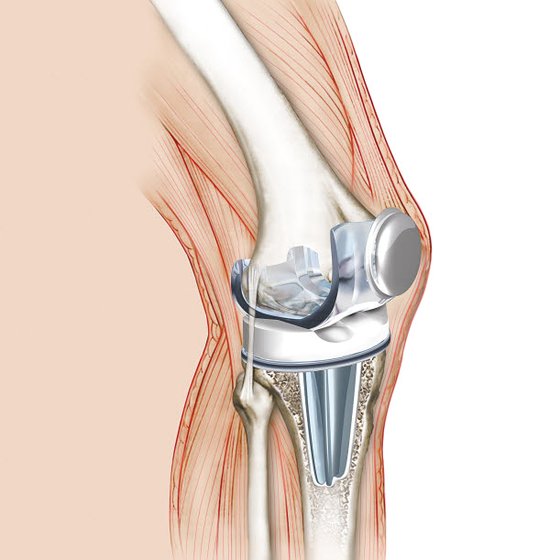

무릎의 연골도 대부분 관절과 동일하게 뼈를 매끄럽고 마찰이 덜가게 생성해 주는 미끄러운 연골 층으로 둘러 축적되어 있어요. 뿐 아니라, 무릎 중앙에는 부가적인 충격 흡수를 전달하는 반월상 연골이라고 하는 두 개의 고무질 반원형 연골 조각이 있어요.

무릎 안에서 체중이 닿지 않는 부위에서 연골을 떼어낸 후 망가진 부분으로 옮겨주는 수술법이라고 합니다. 1회 수술을 통해 자신의 연골을 이식하므로 확실한 연골의 회복을 기대할 수 있으며 손상 연골 부위가 4cm 이하인 경우에 실행해요.